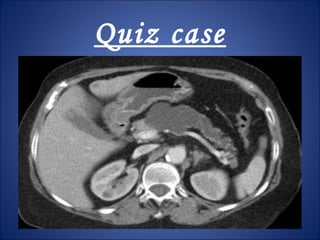

Quiz case